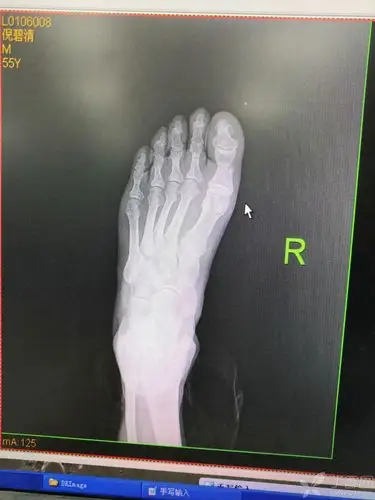

趾骨骨折克氏针内固定手术